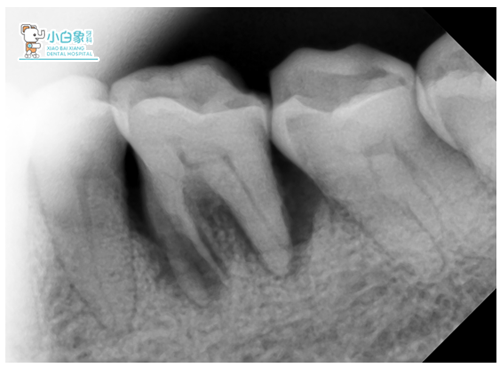

X线片

检查:颌面部未见异常,口内查:36牙体完好,颊舌向松动,叩(土),牙龈无红肿。

X线显示:36近中根见根折影像。

诊断:36根折。